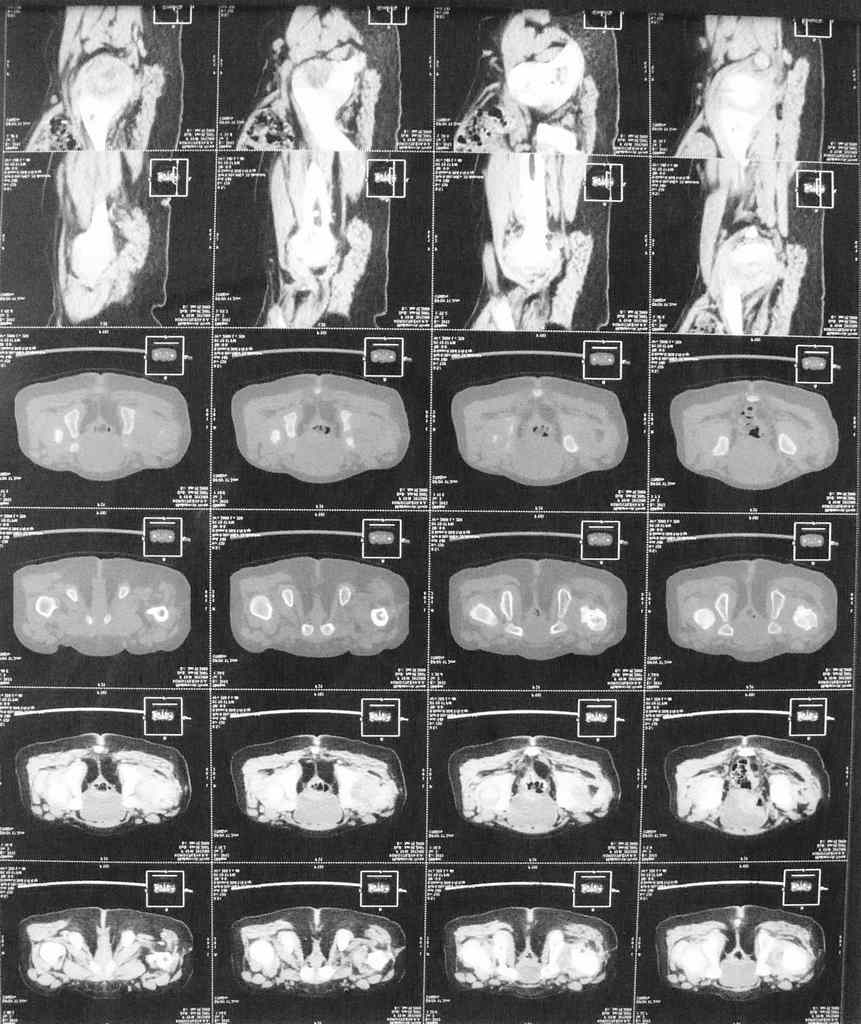

В 6 мес перенесла открытое вправление и деторсионную остеотомию с фиксацией.Через 9 мес фиксатор удален. Предлагается следующее вмешательство в обьеме варизирующей остеотомии. В прищепке КТ и 3Д реконструкция.Помогите советом кто в состоянии. Заранее благодарен. А Рыков

Привет, А.Г.! По представленным КТ можно утверждать, что у ребенка асептический некроз головки бедра. ШДУ явно ниже нормы. Считаю, что в ближйший год нельзя вмешиваться на ТБС и, тем более, делать варизирующую остеотомию. Проведите активное ФТО (цель - улучшить кровоснабжение поясничного отдела позвоночника и ТБС). Постарайся в будущем не облучать ребенка на КТ, лучше МРТ. АИФ